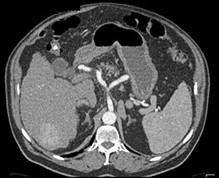

问题 男,44岁,患乙肝多年,现腹痛,腹胀,AFP增高,消瘦、乏力,影像检查如图,最可能诊断是()

选项 A.肝血管瘤 B.肝腺瘤 C.肝转移瘤 D.肝硬变、肝癌 E.肝结节性增生

答案 D